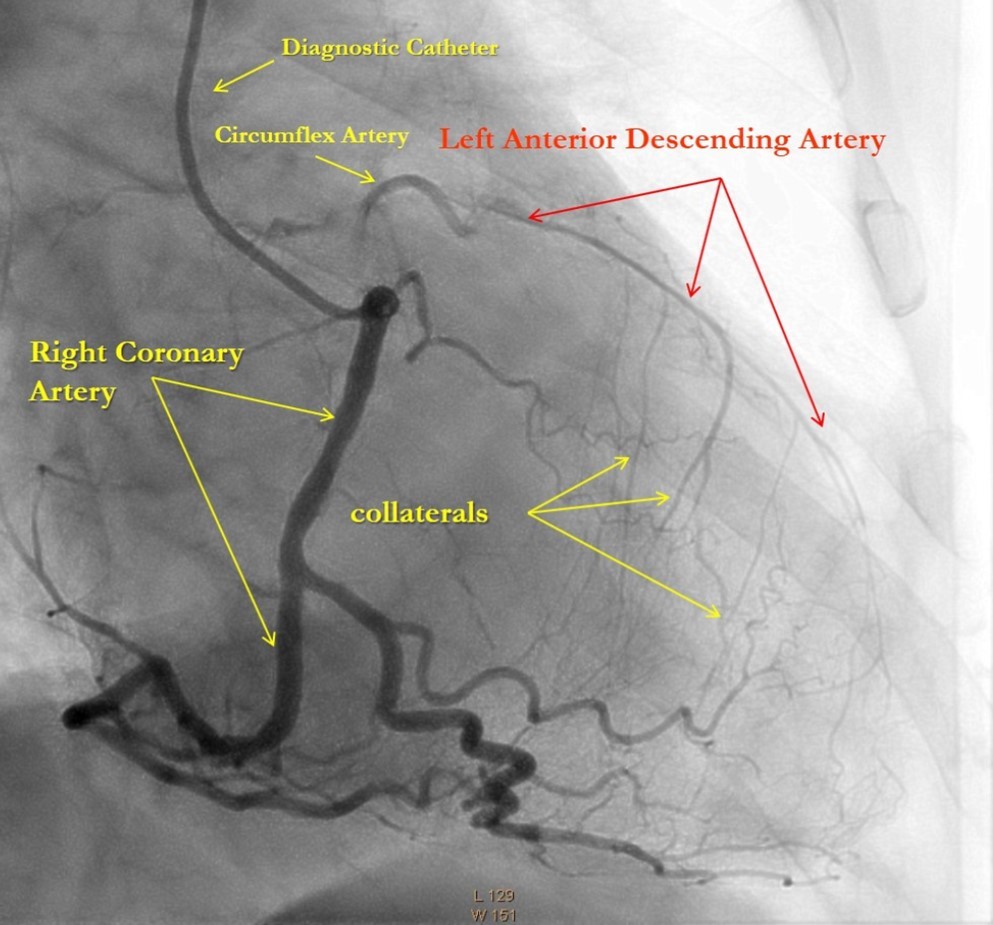

After medical treatment and comparable improvement in the patient's condition, expected risks were re-evaluated. After consulting with the patient and family members (they did not agree to the operation based on past experience) it was resolved to perform repeated CAG and to attempt revascularization of the LAD artery, (stenting). However, repeated CAG additionally revealed chronic 100% occlusion of the LMCA (Figure 1), and also CX occlusion, which was unexpected, and thereby significantly decreasing the likelihood of procedural success. In this case, the patient's heart was supplied only through the right coronary artery, which partially supplies the occluded left anterior descending and circumflex arteries through the contralateral collateral blood flow (Figure 2). Acute LMCA occlusion in most of the cases is fatal and survival is possible only in patients with a dominant RCA providing sufficient collateral formation.

Figure 2.Right Coronary Artery with developed right-to-left collaterals.

Right Coronary Artery with developed right-to-left collaterals.